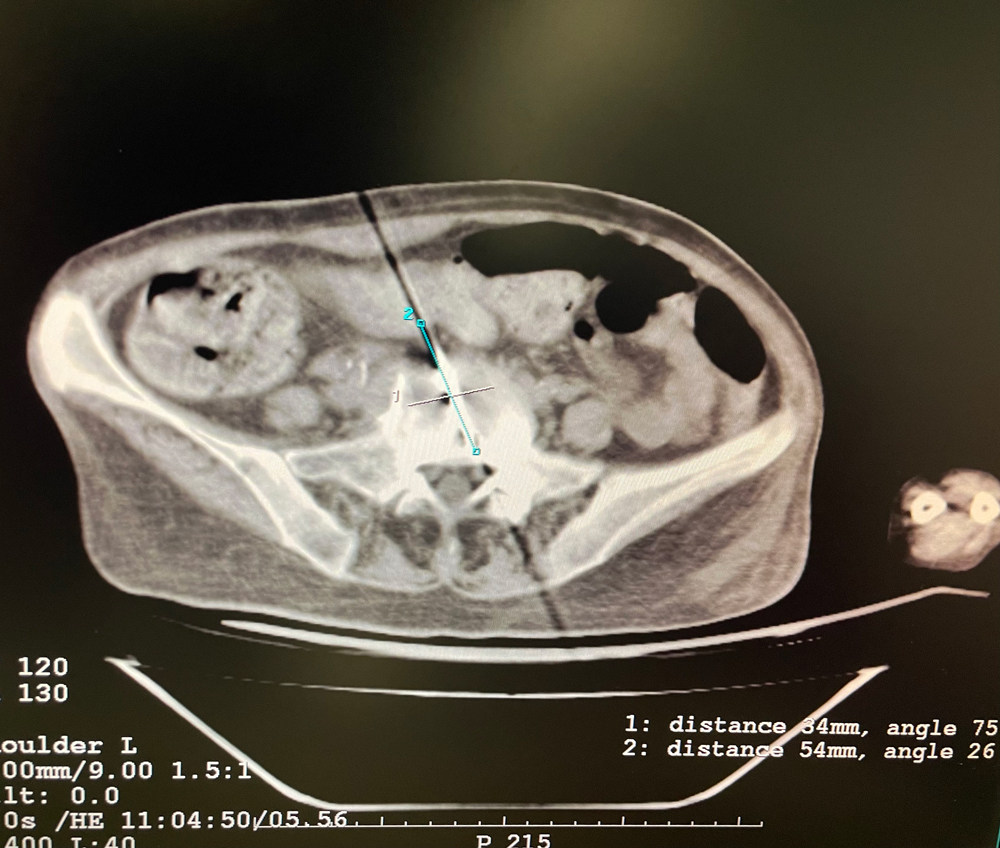

女,56歲,肺轉移瘤,骶骨、左側肋骨各一轉移灶,病灶大小均為5cm。骶骨轉移灶、肋骨轉移灶各進行2個凍融循環(huán)。患者術后狀況良好。

女,42歲,復發(fā)性脂肪瘤,病灶位于右側膝關節(jié),直徑大小13cm。采用雙針方案,共進行6個凍融循環(huán),最大冰球直徑達8.2cm,術中多方位治療全面覆蓋病灶范圍。患者術后狀況良好。